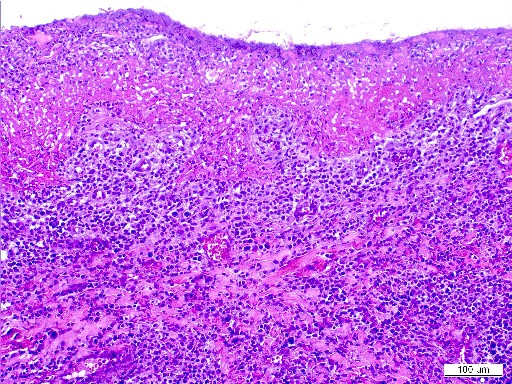

Si bien sería suficiente para establecer el diagnóstico definitivo con la prueba citológica cuando se ha podido observar el agente sospechoso; consideramos que una biopsia acompañada de una tinción inmunohistoquímica confirma los hallazgos citológicos y nos muestre el patrón histopatológico compatible. Además, en nuestra experiencia, nos aporta (con elevada capacidad diagnóstica) el diagnóstico definitivo cuando no se haya podido visualizar el parásito por citología. En este caso el resultado de la biopsia fue el de una dermatosis nodular con un infiltrado rico en linfocitos, células plasmáticas y macrófagos (fig. 6) con amastigotes en el interior del citoplasma que se evidenciaron mediante técnicas de inmunohistoquímica.

| Fig.6.Imagen microscópica de la biopsia de un nódulo. Infiltrado inflamatorio rico en linfocitos; y células plasmáticas. | Fig.7.Imagen del proteinograma con una gran banda de beta y gamma globulinas. |